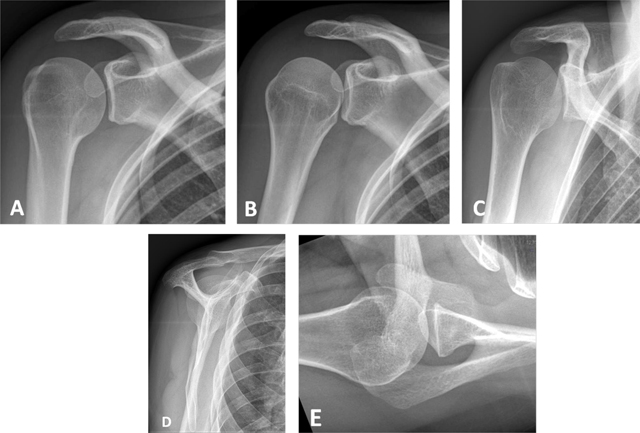

Figure 1

Conventional radiographs of the shoulder. (A) Anteroposterior (AP) view with external rotation; (B) AP with internal rotation; (C) AP with neutral arm position; (D) Lateral view of scapula or ‘Y’ view; (E) Axillary view.